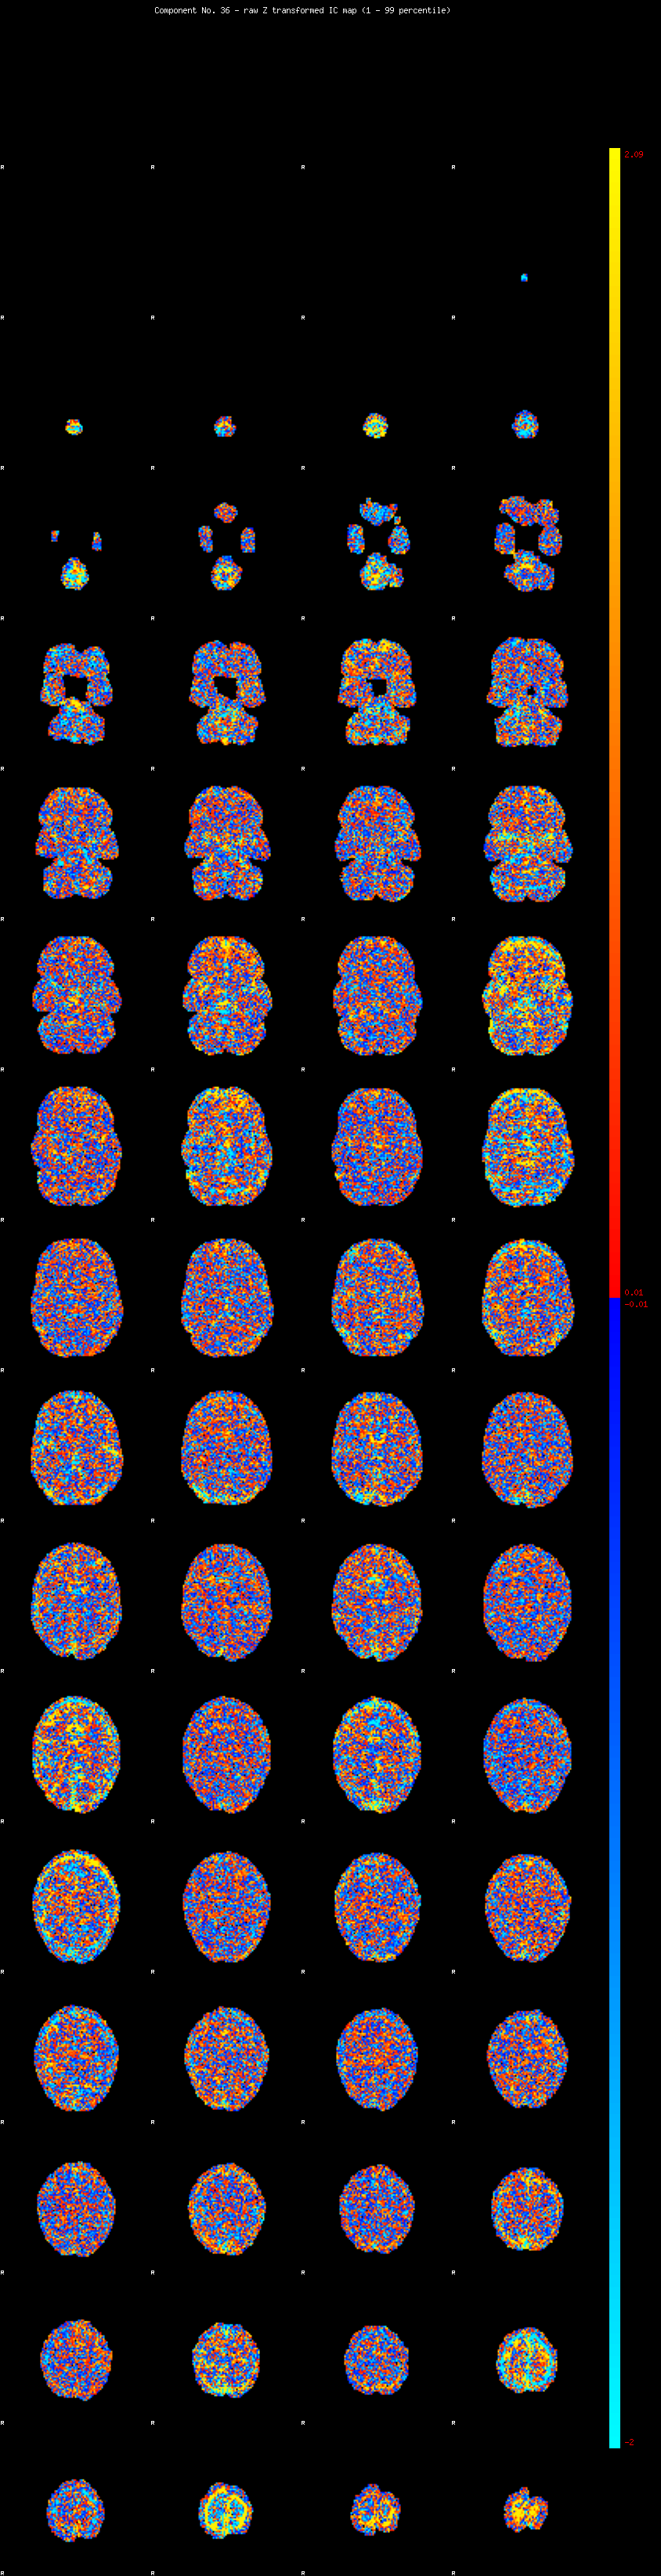

IC_36 Mixture Model fit

Means : 0.000000 2.735653 -2.466137

Vars : 1.000000 2.875196 1.969567

Prop. : 0.925363 0.039922 0.034715